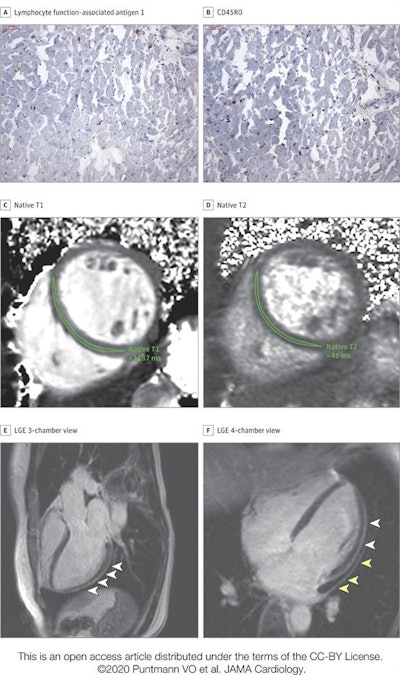

- 78% of patients had abnormal findings on cardiac MRI, including raised myocardial native T1 (73%), raised myocardial native T2 (60%), myocardial late gadolinium enhancement (32%), and pericardial enhancement (22%).

"The most prevalent abnormality [on cardiac MRI] was myocardial inflammation (defined as abnormal native T1 and T2 measures), detected in 60 patients recently recovered from COVID-19 ... followed by regional scar and pericardial enhancement," the group noted.